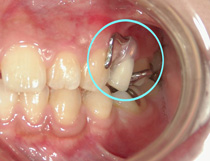

コラム「目立たない入れ歯」の画像